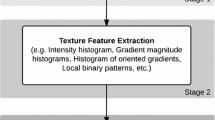

Textural properties of normal and tuberculosis posterior-anterior chest radiographs were looked into in this investigation. The proposed computerized scheme segmented the lung field of interest using a user-guided snake algorithm and extracted the corresponding pixel data. For both normal and tuberculosis radiographs, the grayscale intensity distribution within the region of interest was analyzed to study their respective characteristics, and fed to classifiers for automated classification. Statistically the tuberculosis infected radiographs manifested a higher variance, third moment, entropy and a lower mean value in their intensity distributions, compared to their normal peers. The greater disparities between a particular radiograph and the confidence interval determined by our normal groups on some of the features were observed to be related to the level of haziness at the upper lobe. Lastly, the C4.5 (a decision tree based classifier)-adaboost achieved an accuracy of 94.9% in normal-tuberculosis classification. An integrated index, called tuberculosis index (TI), is proposed based on texture features to discriminate normal and tuberculosis chest radiographs using just one index or number. We hope this TI can be used as an adjunct tool by the radiographers in their daily screening.